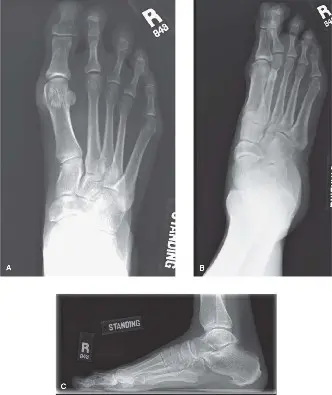

الأشعة السينية (Weight-Bearing Radiographs):

- تُعد الأشعة السينية التي تُجرى أثناء الوقوف (تحمل الوزن) ضرورية. يتم أخذ صور أمامية خلفية (AP)، وجانبية، ومائلة.

- المنظر الأمامي الخلفي (AP View): لتقييم محاذاة مفصل المشط السلامي، وتوسع الأصابع، ووجود إبهام القدم الأروح، ونمط طول الأمشاط (مثل المشط الثاني الطويل). من المؤشرات الشائعة لعدم الاستقرار فقدان التوازي بين المشطين الثاني والثالث.

- المنظر الجانبي (Lateral View): حاسم لتحديد الخلع الجزئي الظهري للسلامية القريبة بالنسبة لرأس المشط. كما يقيم بنية القوس الكلية.

- المنظر المائل (Oblique View): يوفر رؤية إضافية للهياكل العظمية.

توضح هذه الصورة النهج الظهري النموذجي لمفصل المشط السلامي، مع إبراز الهياكل التشريحية ذات الصلة والمناطق المحتملة لشق المحفظة أو إصلاح الصفيحة الأخمصية.